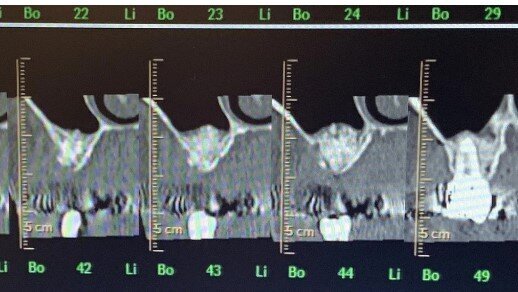

In seguito all’intervento di rialzo di seno mascellare con contestuale GBR è stata eseguita la radiografia ortopanoramica che mostra il corretto riempimento dell’area atrofica del seno mascellare con granuli cortico-spongiosi di osso di origine bovina. Al controllo dopo tre settimane i tessuti molli dell’area trattata risultano perfettamente guariti. La TC Dentalscan effettuata dopo 6 mesi per il controllo della zona rigenerata evidenzia la perfetta guarigione della zona con aumento dello spessore osseo di 5 mm e dell’altezza ossea di 11 mm.

L'evoluzione della tecnica chirurgica nell’approccio attraverso finestra laterale all’osso mascellare per il sollevamento della membrana del seno, ha lo scopo di ridurre le complicanze che possono compromettere l’esito dell’intervento e la sopravvivenza dell’impianto. La chirurgia piezoelettrica ha dimostrato il vantaggio di ridurre drasticamente il tasso di perforazione, aumentando così la percentuale di successo complessivo della tecnica di rialzo di seno mascellare15 (Figg. 19-22).